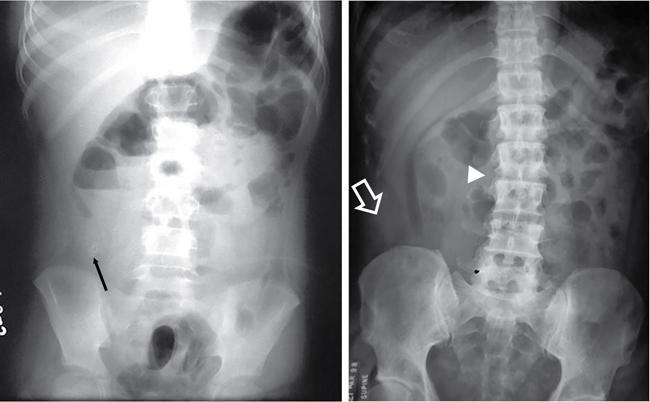

UNDERSTANDING THE ADULT ABDOMINAL RADIOGRAPH: TECHNIQUES AND INTERPRETATION Tanvi Modi Radiography of the abdomen is a common practice for the evaluation of abdominal organs. The anatomy and pathology of digestive, hepatobiliary and genitourinary systems can be assessed using radiographs, either as a stand-alone practice or as a primary imaging modality followed by contrast studies, ultrasound or cross-sectional imaging. In addition, abnormalities of the musculoskeletal or integumentary system can also be deduced on the basis of abdominal radiographs. This chapter intends to give an overview on the techniques and positioning in abdominal radiography as well as interpretation of normal and abnormal features. While superior imaging modalities such as ultrasound, computed tomography (CT), magnetic resonance imaging, capsule endoscopy and the likes have taken over abdominal imaging by and large, radiography still holds a pivotal role in certain situations and conditions, such as: The standard abdominal radiograph is taken in supine position and anteroposterior projection. This is also popularly known as the KUB (kidneys-ureters-bladder) radiograph. Previously, supine as well as erect radiographs were performed in all patients; however, this is not commonly done due to high-radiation dose. For all indications of abdominal radiography, including acute abdomen, supine radiographs are sufficient in terms of radiographic diagnosis, with the exception of perforation for which an erect chest or lateral decubitus radiograph can be performed if there is clinical suspicion. Patient should lie supine on the imaging table with median sagittal plane at right angles to the table and coincident with the midline of the table (Fig. 7.1.1.1). The body is divided into equal right and left halves by the median sagittal which passes through the sagittal suture of the skull. Pelvis should be adjusted so that the anterior superior iliac spines are equidistant from the table top. Gonadal shields, in the case of male patients, should be placed with the upper edge of the shield at the level of pubic symphysis. Although rarely used for female patients, these should be positioned between the anterior superior iliac spines and the pubic symphysis. The centre point of the image receptor should be approximately located at a point 1 cm below the line joining the iliac crests. The X-ray beam should be in a vertical direction, perpendicular to the table top and image receptor at the centre point. Collimation should be such that the soft tissue and subcutaneous region along lateral aspects of the abdominal cavity should be covered within the image. Also, the superior extent involving diaphragm and inferior extent involving the inferior pubic rami is important to look for any lower chest pathologies or any inguinal hernia. 35 × 43 cm (14 × 17 inches) in portrait orientation. On an average, abdominal radiograph exposes a patient to a dose of approximately 1.5 mSv, which is equivalent to 75 chest radiographs or 1/6th dose of a standard CT of the abdomen. The entrance skin dose is approximated to be 4 mGy. At such an effective dose, the additional lifetime risk of fatal cancer is 1 in 30,000. The exposure time is kept short. Patient is asked to exhale completely and hold their breath, with exposure taken at this point of full expiration to ensure imaging of abdominal organs in their natural positions. Modifications of this technique can be made depending on patient habitus and clinical condition. Kilovoltage peak (kVp) should be set to allow adequate visualization of abdominal soft tissue structures as well as semiopaque renal and biliary calculi. Average kVp is set at 70–85 kV. 102 cm (40 inches) Grids are commonly used to reduce scatter radiation. Placement of side marker on the image receptor at the time of radiographic exposure is essential. Bowel pattern depiction should be such that there is minimal lack of sharpness. Standard guidelines for abdominal radiography dictate that the radiograph should extend from the diaphragm up to the level of inferior pubic rami and must include the lateral abdominal wall musculature. The abdomen is divided into four quadrants on the basis of two perpendicular lines (Fig. 7.1.1.7). The vertical line passes through the mid sagittal plane and crosses the umbilicus and symphysis pubis. The horizontal line is a transverse line across the umbilicus at 90 degrees to the vertical line and is situated at the level of L4–L5 intervertebral disc. The quadrants are as follows: Another division system is dividing the abdominopelvic cavity into nine regions using two vertical and two horizontal planes (Fig. 7.1.1.8). The vertical planes, also known as the right and left lateral planes, are parallel to the midsagittal plane between midline and anterosuperior iliac spines on either side. Of the two horizontal planes, the upper transpyloric plane is at the level of lower border of L1 and the lower transtubercular plane is at the level of L5. The nine regions are: On a standard radiograph, the exposure should be such that the stomach, bowel loops, outlines of liver, spleen, kidneys, psoas muscles should be well identified. Also, lumbar transverse processes should be seen. Arch of the pubic symphysis should be visible to evaluate bladder region. A well-centred film without rotation will demonstrate bilaterally symmetrical lower ribs, iliac wings, ischial spines and obturator foramina. Different structures seen on an abdominal radiograph can be classified into five basic densities: Identification of different structures depends on the relative degree of contrast between their densities. The demarcation is clearer in chest and is diminished in abdomen due to relative similar soft tissue density of various structures. On a normal radiograph, relatively large amounts of gas in stomach and colon with minimal small bowel gas can be seen. Further, colonic gas can vary from negligible to extensive, mimicking obstruction pattern; however, usually the gas is enough to delineate colonic haustral pattern. Faecal matter gives a mottled appearance to colonic gas. Short-air fluid levels on an erect radiograph may be seen even in normal cases. The normal appearance of small bowel loops on an abdominal radiograph follows the rule of threes: Stomach is seen in the left upper quadrant and is visualized when distended with air. It is commonly seen extending from T11 to L2 level. Common feature identifying the stomach is the fundal gas which is usually seen as an air fluid level within the gastric lumen. Small bowel loops are distributed to the centre of the abdominal cavity and large bowel loops are peripheral. Duodenum is predominantly situated in right upper quadrant. It extends to left upper quadrant in the region of duodenojejunal flexure. Jejunum occupies the left upper and lower quadrants and is easily identified due to the presence of thick, numerous, closely spaced valvulae conniventes (Fig. 7.1.1.9A). The ileum occupies both lower quadrants and extends into right upper quadrant. Ileum has few and less prominent valvulae as compared to jejunum (Fig. 7.1.1.9B). Ascending and descending colon are retroperitoneal and have relatively fixed positions along lateral aspect of the abdominal cavity on either side. Transverse and sigmoid colon, on the other hand, may have a variable position due to their mobility along mesocolon and redundant pattern. These can be identified with confidence on account of haustrations and faecal matter (Fig. 7.1.1.10). Haustrations are usually well seen in ascending and transverse colon and poorly delineated beyond splenic flexure. Caecum is in the right lower quadrant, though it may be mobile or pulled up. Rectal gas is usually seen in the midline at the level of pelvis and its presence rules out large bowel obstruction. All these positions may vary due to anatomical conditions such as malrotation or pathological conditions, for example volvulus. Liver, spleen and renal outlines cannot be completely traced with precision due to the overlap by bowel loops. On a frontal projection, the liver appears as a triangular structure occupying right and left hypochondrium and epigastric region. Occasionally, the right lobe may be seen extending lower than the right renal shadow. This is a normal variant known as Reidel’s lobe. Gall bladder is situated in the posterior and inferior region of the liver and any pathology of the gall bladder should be looked for in this region. On a lateral radiograph, the gall bladder is anterior to the midcoronal plane. This helps in distinguishing gall bladder calculi from renal calculi, which will be more posteriorly situated. Spleen is seen in left upper quadrant/left hypochondrium, flushed to left lower ribs and left hemidiaphragm. Pancreas is present in the epigastric region (right and left upper quadrants) and is usually not identified in the absence of a pathology. The kidneys are bean-shaped retroperitoneal organs which are seen on either side of the vertebral column and lateral to psoas muscles. Due to the presence of liver on the right side, this kidney is slightly lower in position as compared to its contralateral counterpart. The visualization of kidneys on radiographs is facilitated by the surrounding fatty capsule. Kidneys lie between T11–12 and L2 level, with left kidney 1 cm higher than the right. Psoas muscle shadow can be normally seen along lateral aspect of lumbar spine bilaterally and is mildly concave (Fig. 7.1.1.11). Abdominal wall muscles are not routinely assessed on radiography; however, inclusion of lateral abdominal wall (muscles as well as subcutaneous plane) is a must while performing radiography. The flank stripe or the properitoneal fat stripe is a fat density linear concavity seen along lateral abdominal wall (Fig. 7.1.1.11). It is bound by the paracolic gutters and air-filled ascending and descending colon. All the solid organs in the abdomen are identified due to the fat density outlining them. Distortion of these fat lines helps in identifying organomegaly or focal mass lesions. The dome of urinary bladder is outlined by fat, which aids in differentiating its density from other soft tissue structures of the pelvis. Not all calcifications seen on abdominal radiograph are abnormal. Some may depict age-related changes such as vascular calcifications involving abdominal aorta, pelvic vessels, splenic artery in the region of left upper quadrant. Within the pelvis, phleboliths may be seen and mistaken for urinary calculi. Assessment of lumbosacral spine, iliac bones and femoral heads can be made on the basis of plain radiography. Degenerative changes may be commonly seen. Lower ribs can also be evaluated for pathologies. Dilated small bowel loops with rounded soft tissue density in midline over umbilical region suggests obstruction secondary to umbilical hernia. Pneumoperitoneum must be looked for in all cases of acute abdomen. While erect chest and left lateral decubitus radiographs can detect even 1 mL of free air, there are multiple signs on supine radiograph to suggest this diagnosis, for example Rigler’s sign, falciform ligament sign, football sign (Figs. 7.1.1.24 and 7.1.1.25). Retroperitoneal perforation may demonstrate air outlining psoas muscles and retroperitoneal organs. Small amount of free air may persist in the abdominal cavity up to 3 weeks after surgery, although it usually resolves within a week. Clinical history is important in such cases. Air foci within the bowel wall may represent bowel ischaemia/strangulation. Linear gas patterns in right hypochondrium may be due to two causes, that is pneumobilia and pneumoporta. The former can be seen normally postbiliary surgery, sphincterotomy, ERCP or in the case of abnormal fistulous communication between bowel and biliary tree (Fig. 7.1.1.26A). Pneumoporta (Fig. 7.1.1.26B) is a red flag and warrants further investigation to look for conditions such as mesenteric ischaemia and toxic megacolon. Pneumobilia is more centrally located whereas air shadows in pneumoporta are seen reaching up to periphery of liver. Air foci over renal shadows (Fig. 7.1.1.27), gall bladder or pancreas, in the absence of recent procedural history, suggest fulminant infection and mandate urgent intervention. Central midline calcific foci between T9 and T12 vertebrae can be attributed to calcific pancreatitis (Fig. 7.1.1.28). In the left upper quadrant, areas of calcification seen involving a shrunken spleen may be seen in autosplenectomy. In right upper quadrant, calcified gall stones may be seen. These tend to be small, multiple, uniformly circumscribed and ring-like in appearance with central translucency (Fig. 7.1.1.29A). Mercedes Benz sign, a triradiate pattern of gas lucency, is associated with gallstones. In contrast, renal calculi are more commonly solitary, irregular, of homogenous density, conform to renal calyceal or pelvic outline (Fig. 7.1.1.29B) and are sometimes of staghorn configuration. On lateral view, the gall stones are more anteriorly located as compared to renal calculi, which may be partly superimposed on lumbar vertebrae. Ureteric calculi tend to overlap bony structures such as lumbar transverse processes (Fig. 7.1.1.29B) or sacroiliac joints. Extensive or patchy, curvilinear calcification of gall bladder wall is known as porcelain gall bladder which is often associated with malignant transformation. Calcification involving adrenal glands may be secondary to infection or haematoma, or a congenital condition known as Wolman’s disease where there is bilateral involvement. Discontinuous discrete midline tram track calcification in the abdomen may indicate atherosclerotic changes in abdominal aorta and branch vessels. However, when the calcification is in a globular pattern and seen below the level of L2 vertebra, aortic aneurysm should be suspected (Fig. 7.1.1.30). Appendicoliths, though not commonly seen, may sometimes be detected in right iliac region. Pelvic calcifications: vesical calculi, distal ureteric or vesicoureteric junction calculi, calcified fibroids, ovarian dermoid with tooth-like calcifications (Fig. 7.1.1.31) may be the cause of abdominal pain and should be diligently looked for. Vesical calculi are usually more large and central in location whereas calcification due to fibroids may be more lateral. Schistosomiasis is another cause of bladder wall calcification, as is calcification of bladder tumours. Phleboliths tend to be bilaterally symmetrical, with a lucent centre unlike ureteric calculi. While it is believed that phleboliths are located below the level of ischial spines and ureteric calculi above, this is not always true and should be confirmed with CT. Fluid may collect adjacent to properitoneal fat line, forming a linear soft tissue density separating the fat line from the ascending or descending colon. Hellmer’s sign demonstrates medial displacement of lateral edge of liver (hepatic angle), due to fluid collection or ascites. Gross ascites may appear as generalized abdominal haziness or diffuse increased density of pelvis. Abscesses can involve any solid organ and in such cases may be difficult to demonstrate on plain radiography alone. Enlargement of organ or faint gas densities within can be suggestive of the same. In the case of peritoneal abscess, mottled density due to air, fluid and necrotic contents point towards this diagnosis, especially in right iliac fossa in association with appendicitis. Retroperitoneal abscess, similar to any retroperitoneal mass, may cause displacement of retroperitoneal structures (Fig. 7.1.1.32). Subdiaphragmatic abscesses may show concomitant ipsilateral pleural effusion (Fig. 7.1.1.33). These should be differentiated from Chilaiditi syndrome. Fluid and soft tissue lesions present with the same density on radiographs. While it is difficult to characterize the lesion and organ of origin, clues for the same can be provided by organomegaly (Fig. 7.1.1.34), distortion of fat surrounding solid organs, displacement of bowel loops or solid organs. For example, a retroperitoneal lesion may cause anterior or inferior displacement of kidney, a pelvic mass may cause upward displacement of small bowel loops. Different densities such as fat or calcification may help in identifying organ of origin (e.g. fat and tooth densities seen in ovarian dermoid). Convexity of margins of psoas muscle on an abdominal radiograph can be due to haematoma, abscess or intramuscular tumour. Radiographs are performed for the initial diagnosis of foreign body in the abdomen including type, number of foreign bodies, location, size and shape (Fig. 7.1.1.35). Radiolucent foreign bodies such as wood, plastic, chicken bones will not be easily identified on radiography. Low kVp (65–70 kVp) can increase contrast and help identify these objects. In addition to an abdominal radiograph, chest radiography is also performed to exclude aspiration or oesophageal location of foreign body. Ingested or introduced foreign bodies may cause complications such as obstruction, perforation, fistula formation and sepsis. Hence, once their presence is confirmed, follow up radiography must be performed until they are eliminated. One must look for fractures/dislocation injuries involving the vertebrae or pelvic bones, especially after history of trauma. Lucent expansile lesions or sclerotic bony deposits which represent neoplasms, absent pedicle sign in cases of metastasis, metabolic bony changes such as rugger jersey appearance, Paget’s disease, arthropathies such as ankylosing spondylitis with bamboo spine appearance and sacroiliitis (Fig. 7.1.1.36) are some of the conditions which may be diagnosed based on an abdominal radiograph. Overlap of bowel loops over iliac blades may lead to a misdiagnosis of lucent lesions and should be evaluated with caution. Basal pneumonia may be the cause of acute abdominal pain and should be looked for in abdominal radiography. Similarly, pleural effusion, pericardial effusion, calcified pleural plaques, achalasia, interstitial fibrosis are few other findings that can be seen in lower chest on an abdominal radiograph. Basilar atelectasis can give a deceptive appearance of pneumoperitoneum (Fig. 7.1.1.37). Surgical clips, commonly in right hypochondrium after cholecystectomy, drainage tubes, ventriculoperitoneal shunts, femoral line catheters, IVC filters, stents (vascular, renal, biliary) (Fig. 7.1.1.38), stoma bags, contraceptive devices are some structures that may be seen in an abdominal radiograph. Correct knowledge of patient history and normal locations of these structures prevents misdiagnosis. Certain artefacts may be projected upon the radiograph due to surface structures such as trouser buttons, body piercing, sequins over clothing and should not be considered as a pathology. Multiple skin surface nodules in cases of neurofibromatosis, soft tissue focal swellings, such as abscesses, lipomas, haematomas, desmoid tumours and malignant lesions may be incidentally seen on radiography. These can be further evaluated using ultrasound or CT. Subcutaneous emphysema is another finding that may be seen in lower abdominal wall secondary to retroperitoneal perforation or diffusely along abdominal wall in the case of bowel perforation (Fig. 7.1.1.39). Foreign bodies such as bullets and pins may be seen lodged in abdominal wall. A systematic approach to abdominal radiographs is important for accurate diagnosis as follows: Despite the development of newer techniques for imaging of the abdomen, plain radiography still holds an important place in the initial assessment of acute abdomen. Positive and negative findings on an abdominal radiograph can direct further investigation. Ideal positioning, recognition of normal appearances and keen scrutiny for pathologies is a sine qua non for radiologists reading a plain film of the abdomen. OESOPHAGOGRAM Padma V. Badhe, Vikram Reddy, Sultan Moinuddin Shaukatali, Zillani Alam, Ravi Varma, Abhishek Bairy, Dasari Ravikiran, Revati Tekwani, Soniya Patankar, Megha Nair, Gautham Shankar Oesophagogram is the process of obtaining radiological images and simultaneous motion recording to evaluate function and disorders of pharynx, oesophagus and proximal stomach. Oesophagogram is usually done primarily to evaluate dysphagia. Some of the common indications are oesophageal motility disorders, strictures, gastro-oesophageal reflux disease (GERD) and suspected masses. It can also be used to detect uncommon anomalies like vascular rings/slings and aberrant anatomy. It also helps to evaluate further in cases where there is inability to pass upper GI scope. Double-contrast oesophagogram is mainly indicated in early mucosal disease like erosion, polyp, infection and tumours. If a motility disorder is suspected, dynamic technique (e.g. videofluoroscopy) is used for dysphagia or aspirations in cases of stroke, neuromuscular disorders, post head and neck surgery or radiation. Barium oesophagogram is contraindicated in suspected cases of perforation and tracheoesophageal fistula, aspiration, rarely if there is hypersensitivity to barium suspensions. It is also contraindicated in suspected oesophageal perforation where a water-soluble contrast agent is more suitable. However, ionic water-soluble contrast agent is better avoided in cases of aspiration or fistula with airway. The contrast examination of the pharynx is dangerous in cases of acute epiglottitis and must be ruled out on plain radiograph. An 80% w/v barium suspension is used in full column views. However, 200%–250% w/v barium suspensions is usually required for mucosal relief films. The barium sulphate mixture is fed to the patient either by spoon, by glass, or through a drinking straw, depending on its consistency. In videofluoroscopy, the pharyngeal phase of swallowing is usually safer with barium pudding than with thick barium and safer with thick barium than with thin barium. However, if the major abnormality is poor pharyngeal contraction leading to stasis in the piriform sinus (and epiglottic tilt is normal), a thin liquid is safer. Epiglottic motility is better assessed with thin barium because thick barium often obscures the epiglottic tip. Fluoroscopic equipment capable of cine fluoroscopy and capability for rapid sequence spot images (high frame rate) is needed for this examination, Barium suspension, straw, glass, Lead apron and radiation protective equipment. The patients are instructed to fast after midnight before the day of the examination. The pharynx should be made as dry as possible during the examination as high-density barium adheres to dry pharyngeal mucosa. Activities like smoking, chewing gum and lozenges must be abstained before the procedure as they impair barium coating by increasing the salivary secretion. Regular oral medications must be taken with sips of water; however, insulin must be skipped on the morning of examination. The major principles of a good oesophagogram includes mucosal coating, distension and projection. A routine oesophagogram consists of screening of the oral, pharyngeal and oesophageal phases of swallowing, single and double-contrast examination of pharynx, single contrast, double-contrast and mucosal relief views of the oesophagus. In cases of dysphagia, the examination is tailored depending on whether the symptoms are either pharyngeal or oesophageal and initial fluoroscopic findings. If patients’ symptoms are suggestive of oral or pharyngeal disorder then pharynx is evaluated first. Similarly, if patient is suspected to have thoracic oesophageal disease then, double-contrast examination of the oesophagus is performed before the pharyngeal evaluation. During an oesophagogram the positioning of the patient varies according to the type of examination (Table 7.1.2.1).